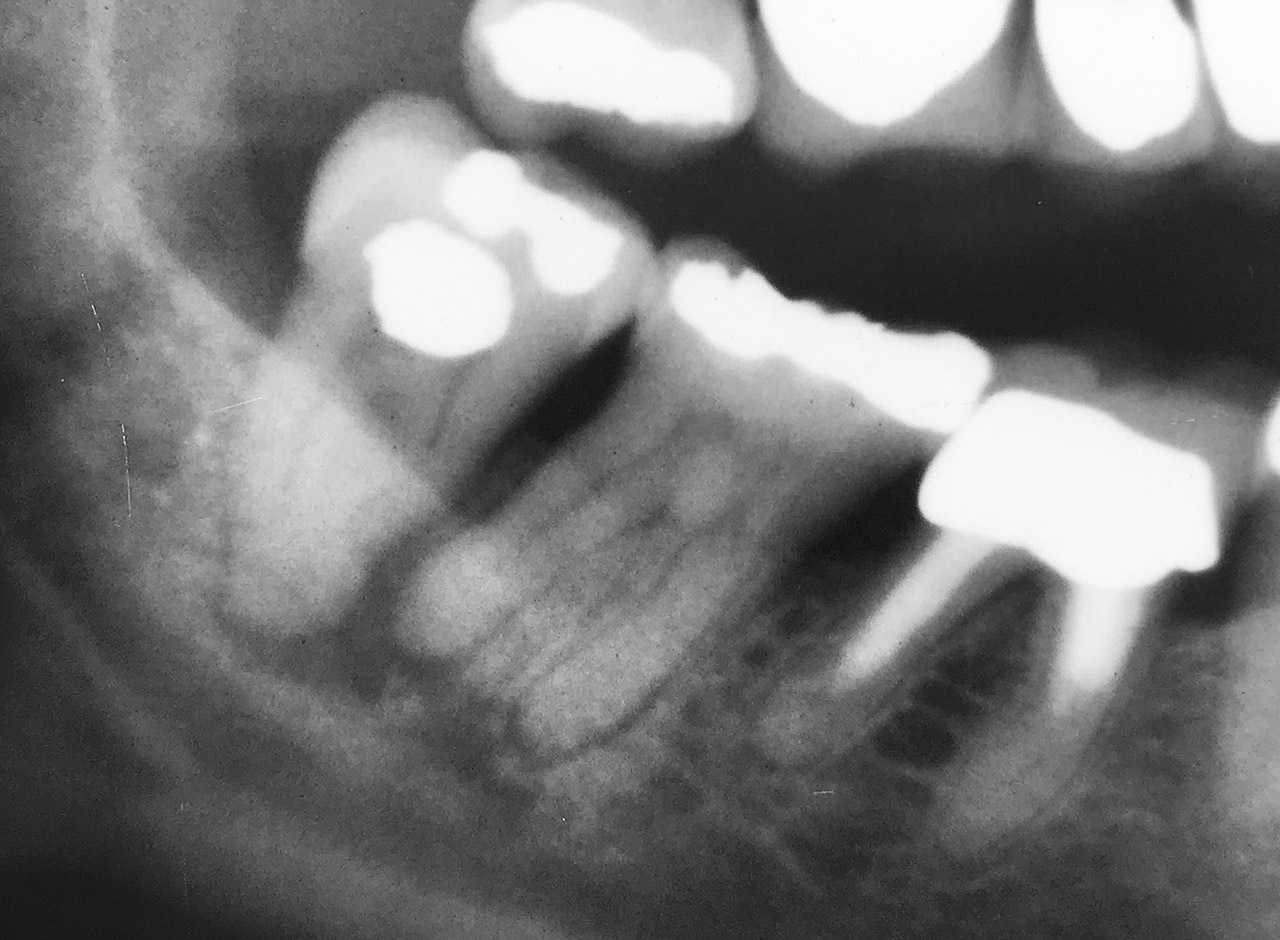

Endodontie/Wurzelbehandlung:

Befund: Aufbißschmerz und Schwellung auf Zahn 46. Frisch zementierte Krone (alio loco).

Therapie: Abnahme der Krone, Entfernung der Zementreste, Revision der insuffizienten Wurzelbehandlung.

Glasfaserstifte und neue Krone, beides adhäsiv zementiert.